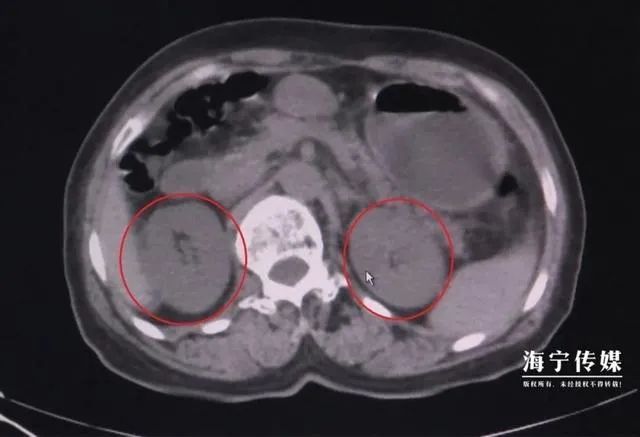

到了海宁中医院经过诊断,李阿姨的肾功能指标已经到了肾功能衰竭的第五期,也就是我们日常听到的尿毒症期。医生告诉李阿姨,刀豆中含有生物碱,如果不充分煮熟,生物碱不能完全分解,人吃了之后就会出现中毒症状。

毒素被吸收导致了急性的肾功能衰竭,从而也就排不出尿液了。李阿姨需要经过一段时间的透析治疗,肾功能才能恢复。